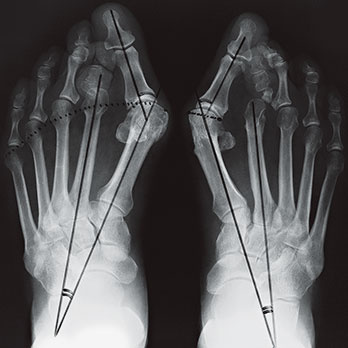

Abb. 1

Hallux valgus

Geringe Deformitäten mit wenig Beschwerden können mit Fussgymnastik, Schuhanpassungen oder häufig mit einer spreizfusskorrigierenden Schuheinlage, welche der Orthopädietechniker oder -schuhmacher anfertigt, korrigiert, respektive verbessert werden. Gröbere Verformungen bedürfen einer operativen Korrektur. Es gibt verschiedene Operationsverfahren. Ziel ist es, die Vorfussverbreiterung zu reduzieren und die Zehen wieder besser auszurichten. Die sanfteste operative Korrektur ist die Gelenks- oder Mittelfussköpfchen-Remodellierung. Hier wird das durch Verknöcherungen deformierte Köpfchen oder das gesamte Gelenk wieder in die ursprüngliche Form gebracht. Mit grösserem Aufwand werden Fehlstellungen durch Verschiebekorrekturen auf verschiedenen Höhen des Grosszehen-Mittelfussknochens sowie der Zehenglieder durchgeführt (Abb. 1). Diesbezüglich sind sehr viele verschiedene Operationsverfahren möglich. Ziel all dieser Korrekturen ist es, dass die ursprüngliche Fussform mit den physiologischen Auflageorten und der Kraftverteilung wieder hergestellt wird. Die aktuell meistgenutzte Korrekturoperation mit guten Möglichkeiten ist die Methode nach SCARF (Abb. 2), welche vom französischen Orthopäden Dr. Samuel Barouk entwickelt wurde. Sie beinhaltet eine seitliche, Z-förmige Mittelfussdurchtrennung mit Parallelverschiebung des vorderen Gelenksfragments zur 2. Zehe hin. Die Korrekturstellung wird anschliessend mit Spezialschrauben fixiert, und zur Entlastung des operierten Vorfusses wird ein Spezialschuh während 6 Wochen getragen.